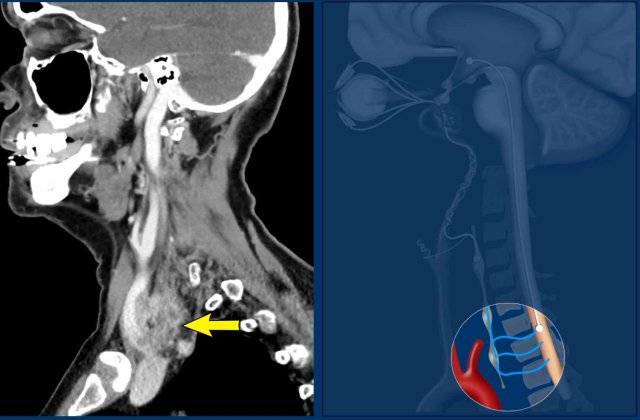

Case

Images of a patient with a rapidly enlarging neck mass, who complaints of swallowing problems and hoarseness.

The physical examination also detected a partial Horner with ptosis and miosis.

Images

CT of the head and neck shows an invasive thyroid mass with paralaryngeal and prevertebral extension and involvement of thyroid cartilage (yellow arrowhead).

There is a tumor thrombus in the jugular vein (black arrow).

Continue with the next images...

Notice the invasion of the thyroid cartilage (yellow arrowhead).

On the edge of the scan there was a brain metastasis.

Discusson

The Horner is caused by influencing the preganglionic system.

There are numerous fibers connecting the middle cervical ganglion (MCG) and inferior cervical ganglion (ICG), which are located anterior and posterior to the vertebral artery.

Final diagnosis

Anaplastic thyroid carcinoma.

This cancer is one of the most aggressive tumors and has a bad prognosis.